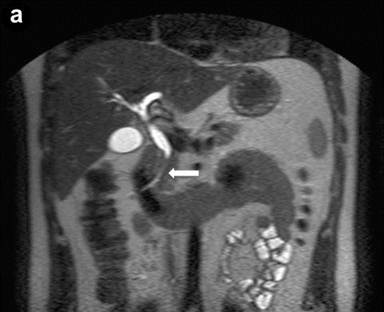

A 24-year-old man presenting with jaundice and elevated levels of IgG4 (366 mg/dL; reference range: 8-140 mg/dL). Magnetic resonance cholangiopancreatography (MRCP) was requested; the T2-weighted coronal scan (Image 1a) showed dilated intra- and extra-hepatic bile ducts with an abrupt stricture (arrow) of the intrapancreatic common bile duct; the pancreatic duct was narrowed throughout its course. Subsequent EUS (Image 1bc) revealed a diffusely and substantially enlarged pancreatic gland (arrowheads) with echopoor echotexture and a normal main pancreatic duct having a diameter of 1.3 mm (Image 1b, arrow), measured with calipers (Image 1c, arrow). Hyperechoic septa were well visible in the enlarged gland. Stenosis of the distal bile duct was due to a diffuse thickening of the wall with an intermediate echopoor layer, and echorich outer and inner layers ("sandwich-pattern") (Image 1d, arrowheads).